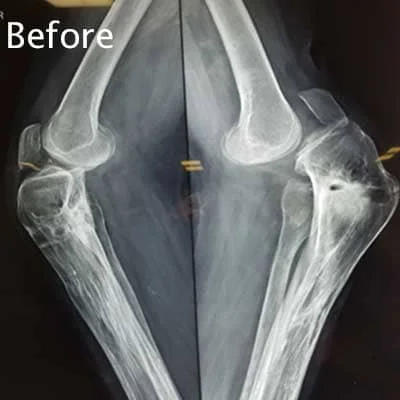

Complex Orthopaedic Surgery

• Removing the damaged articular cartilage (a plate that assists with smooth leg movement)

• Smoothening of the damage to the femur and tibia: These damages might be caused by degenerative diseases like arthritis.